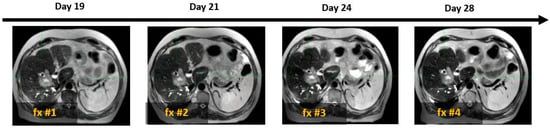

As illustrated in Figure 4, SPIONs ensured consistent tumor visibility throughout the entire treatment course of the MR-guided liver SBRT, which had a median duration of 15 days (ranging from 5 to 28 days).

Figure 4. Example of four daily MR image sets used for online treatment plan adaptation targeting solitary colon cancer metastasis (white arrow) with SBRT (50 Gy in 4 fractions). Days 19, 21, 24, and 28 indicate the time elapsed since Ferumoxytol® injection, corresponding to sequential SBRT fractionation (fx).